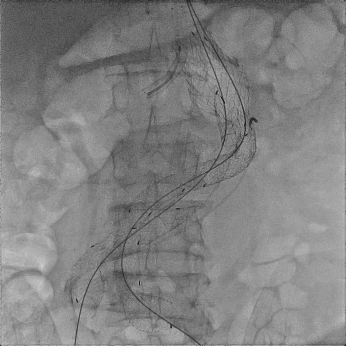

▲ 术中DSA(图2)

王兵教授带领的血管外科团队与胡强夫教授带领的麻醉团队协同配合,应用微创腔内技术,即双上肢动脉穿刺,双下肢股部微小切口,成功的将腹主动脉覆膜支架植入瘤体内,并应用2枚小型覆膜支架保留了右侧肾脏供血,取得了满意效果(图2)。术后,在施敏护士长带领的护理团队的精心呵护下,患者恢复良好,腹痛症状缓解,腹中的“定时炸弹”被成功拆除,出院时复查结果显示效果良好(图3)。